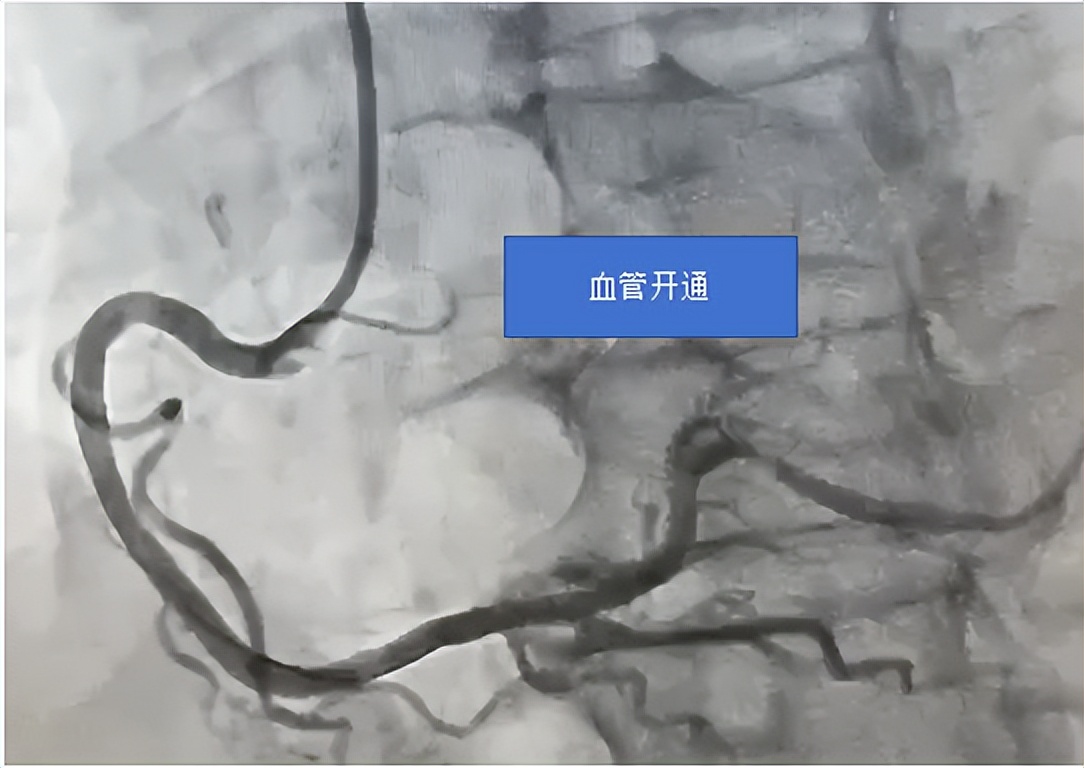

患者到达后,心血管内科介入团队迅速行动,与时间赛跑。他们争分夺秒,迎难而上,凭借精湛的医术与默契的配合, 从患者抵达医院门口到导引导丝通过闭塞血管(D - to - W 时间,国家胸痛中心要求 90 分钟以内),仅仅用了 23 分钟;球囊扩张时间(D - to - B 时间)也仅为 35 分钟。在各急救单位、部门的紧密协作下,患者的生命得以快速而有效地挽救。